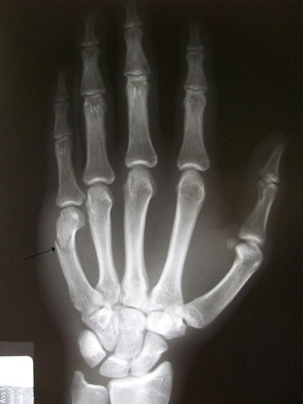

This next graphic shows you an X-ray of a fracture of the fifth metacarpal bone. The metacarpal bones make up the flat part of your hand. Doctors often call this fracture a Boxer’s fracture because it usually happens when a person forcefully hits a hard object with their fist. If you look carefully at the top of the longest bone on your left, you can also see that this fracture has caused the bone to bend, requiring surgery. The finger, and possibly the entire hand, will then need to be immobilized while the bone heals, leading to hand weakness.

Fracture of the 5th Metacarpal